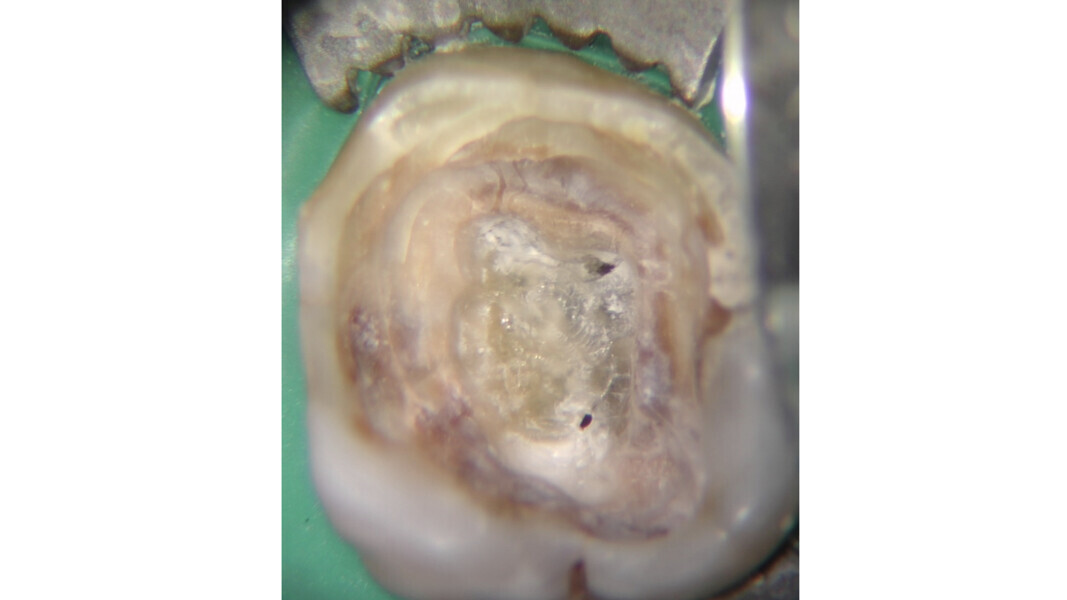

The pulp chamber floor reflects light differently to calcified tissue, providing a valuable guide to the operator. The pulp chamber floor always appears darker and more opaque compared with calcified tissue, which tends to be shiny and have a vitrified appearance (Figs. 15–20). The use of a light source together with a magnifying system greatly eases this evaluation, and it should be considered a mandatory device for anyone performing endodontic treatment.

Fig. 16: Intermediate phase of treatment, after pre-endodontic reconstruction, access cavity preparation and preliminary canal shaping. Note the presence of a pulp stone on the floor of the chamber with a translucent appearance.

Fig. 19: Appearance of the pulp chamber after obturation. Note the typical opacity of the floor without any calcification.